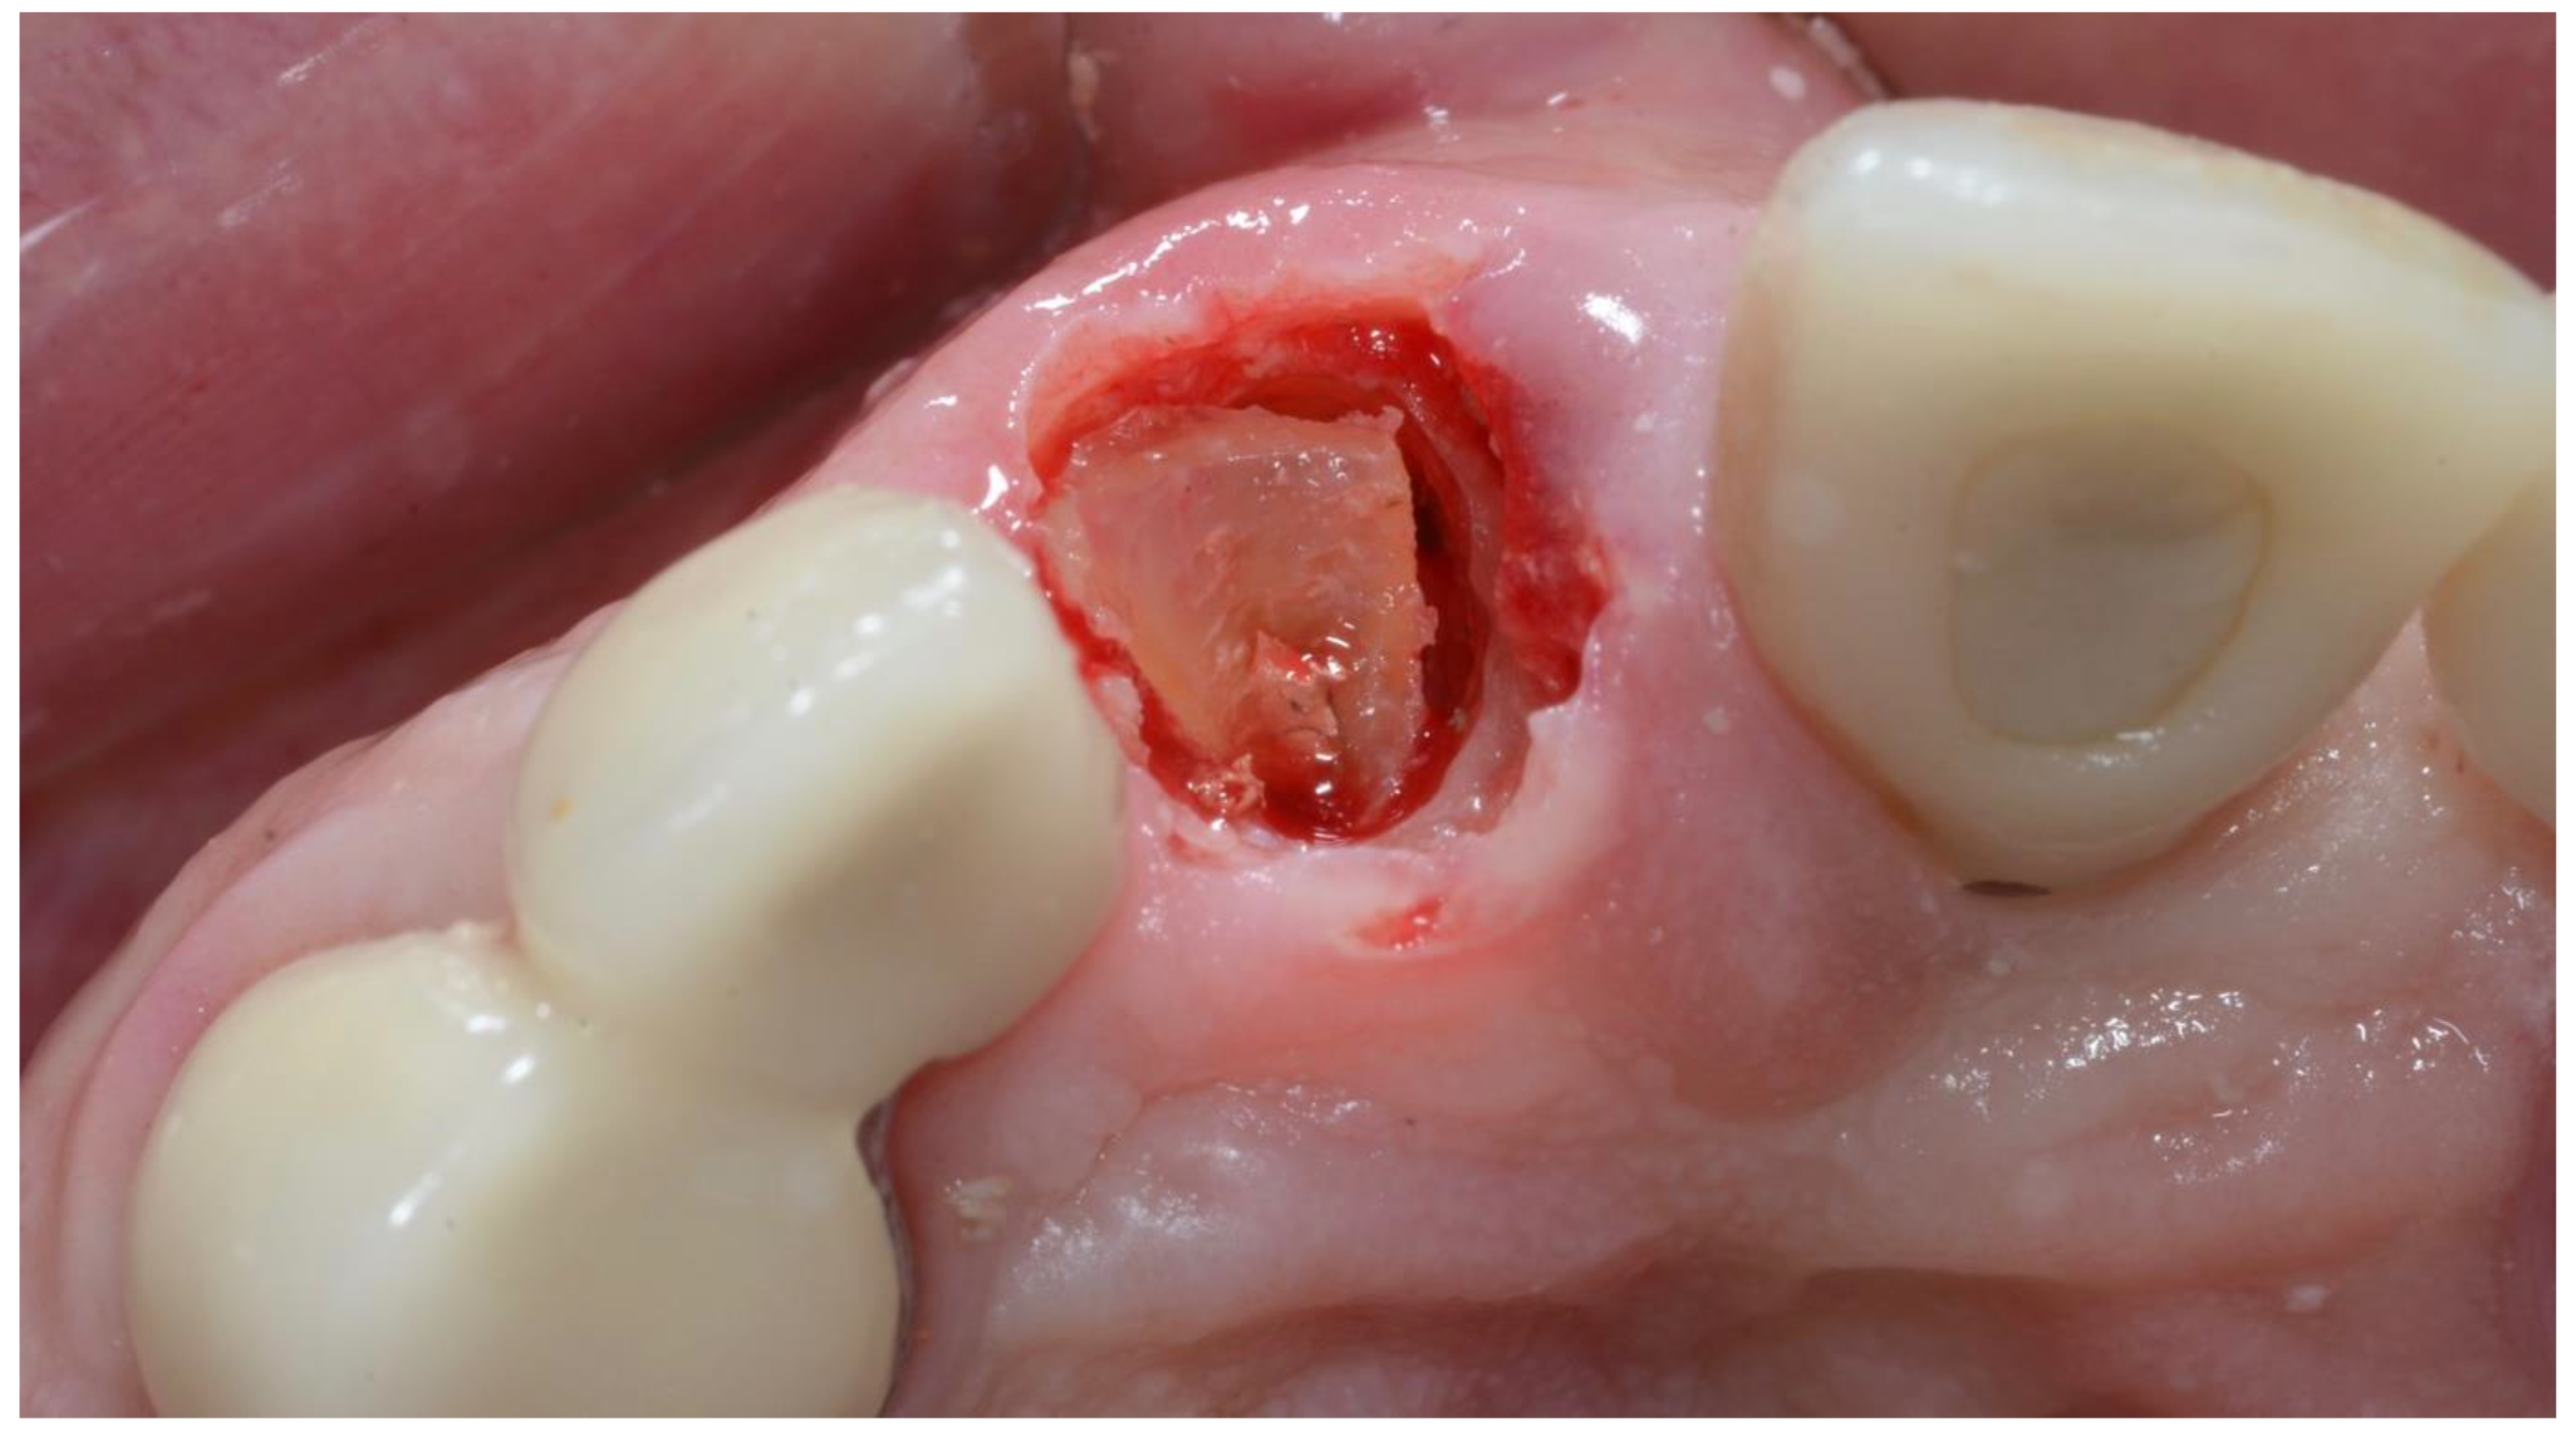

2.1. Surgical Technique